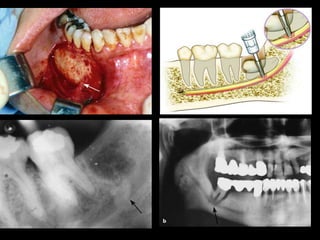

 Rare complication associated mainly with the

extraction of impacted mandibular third molars.

 excessive force with the

elevator

 Inadequate pathway for

removal of the impacted

 ankylosed tooth

 Weak mandible due to artophy or when other

impacted teeth are also present, or in the case of

extensive edentulous regions and the presence of

large pathologic lesions in the area of the tooth to

be extracted

 When a fracture occurs during the extraction,the tooth must

be removed to avoid infection along the line of the fracture.

 Afterwards, depending on the case, stabilization by way of

intermaxillary fixation or rigid internal fixation of the jaw

segments is applied for 4–6 weeks

 Broad-spectrum Antibiotics .

 Displacement of Impacted Tooth, Root, or Root Tip into Maxillary

Sinus removal better to done immediately, to avoid infection of

the sinus

 The exact position of the tooth or root tip must be confirmed with

radiographic examination.

 Removal of the tooth or root from the maxillary sinus is usually

achieved with Caldwell–Luc approach.

 Antibiotic treatment and nasal decongestants are also

administered